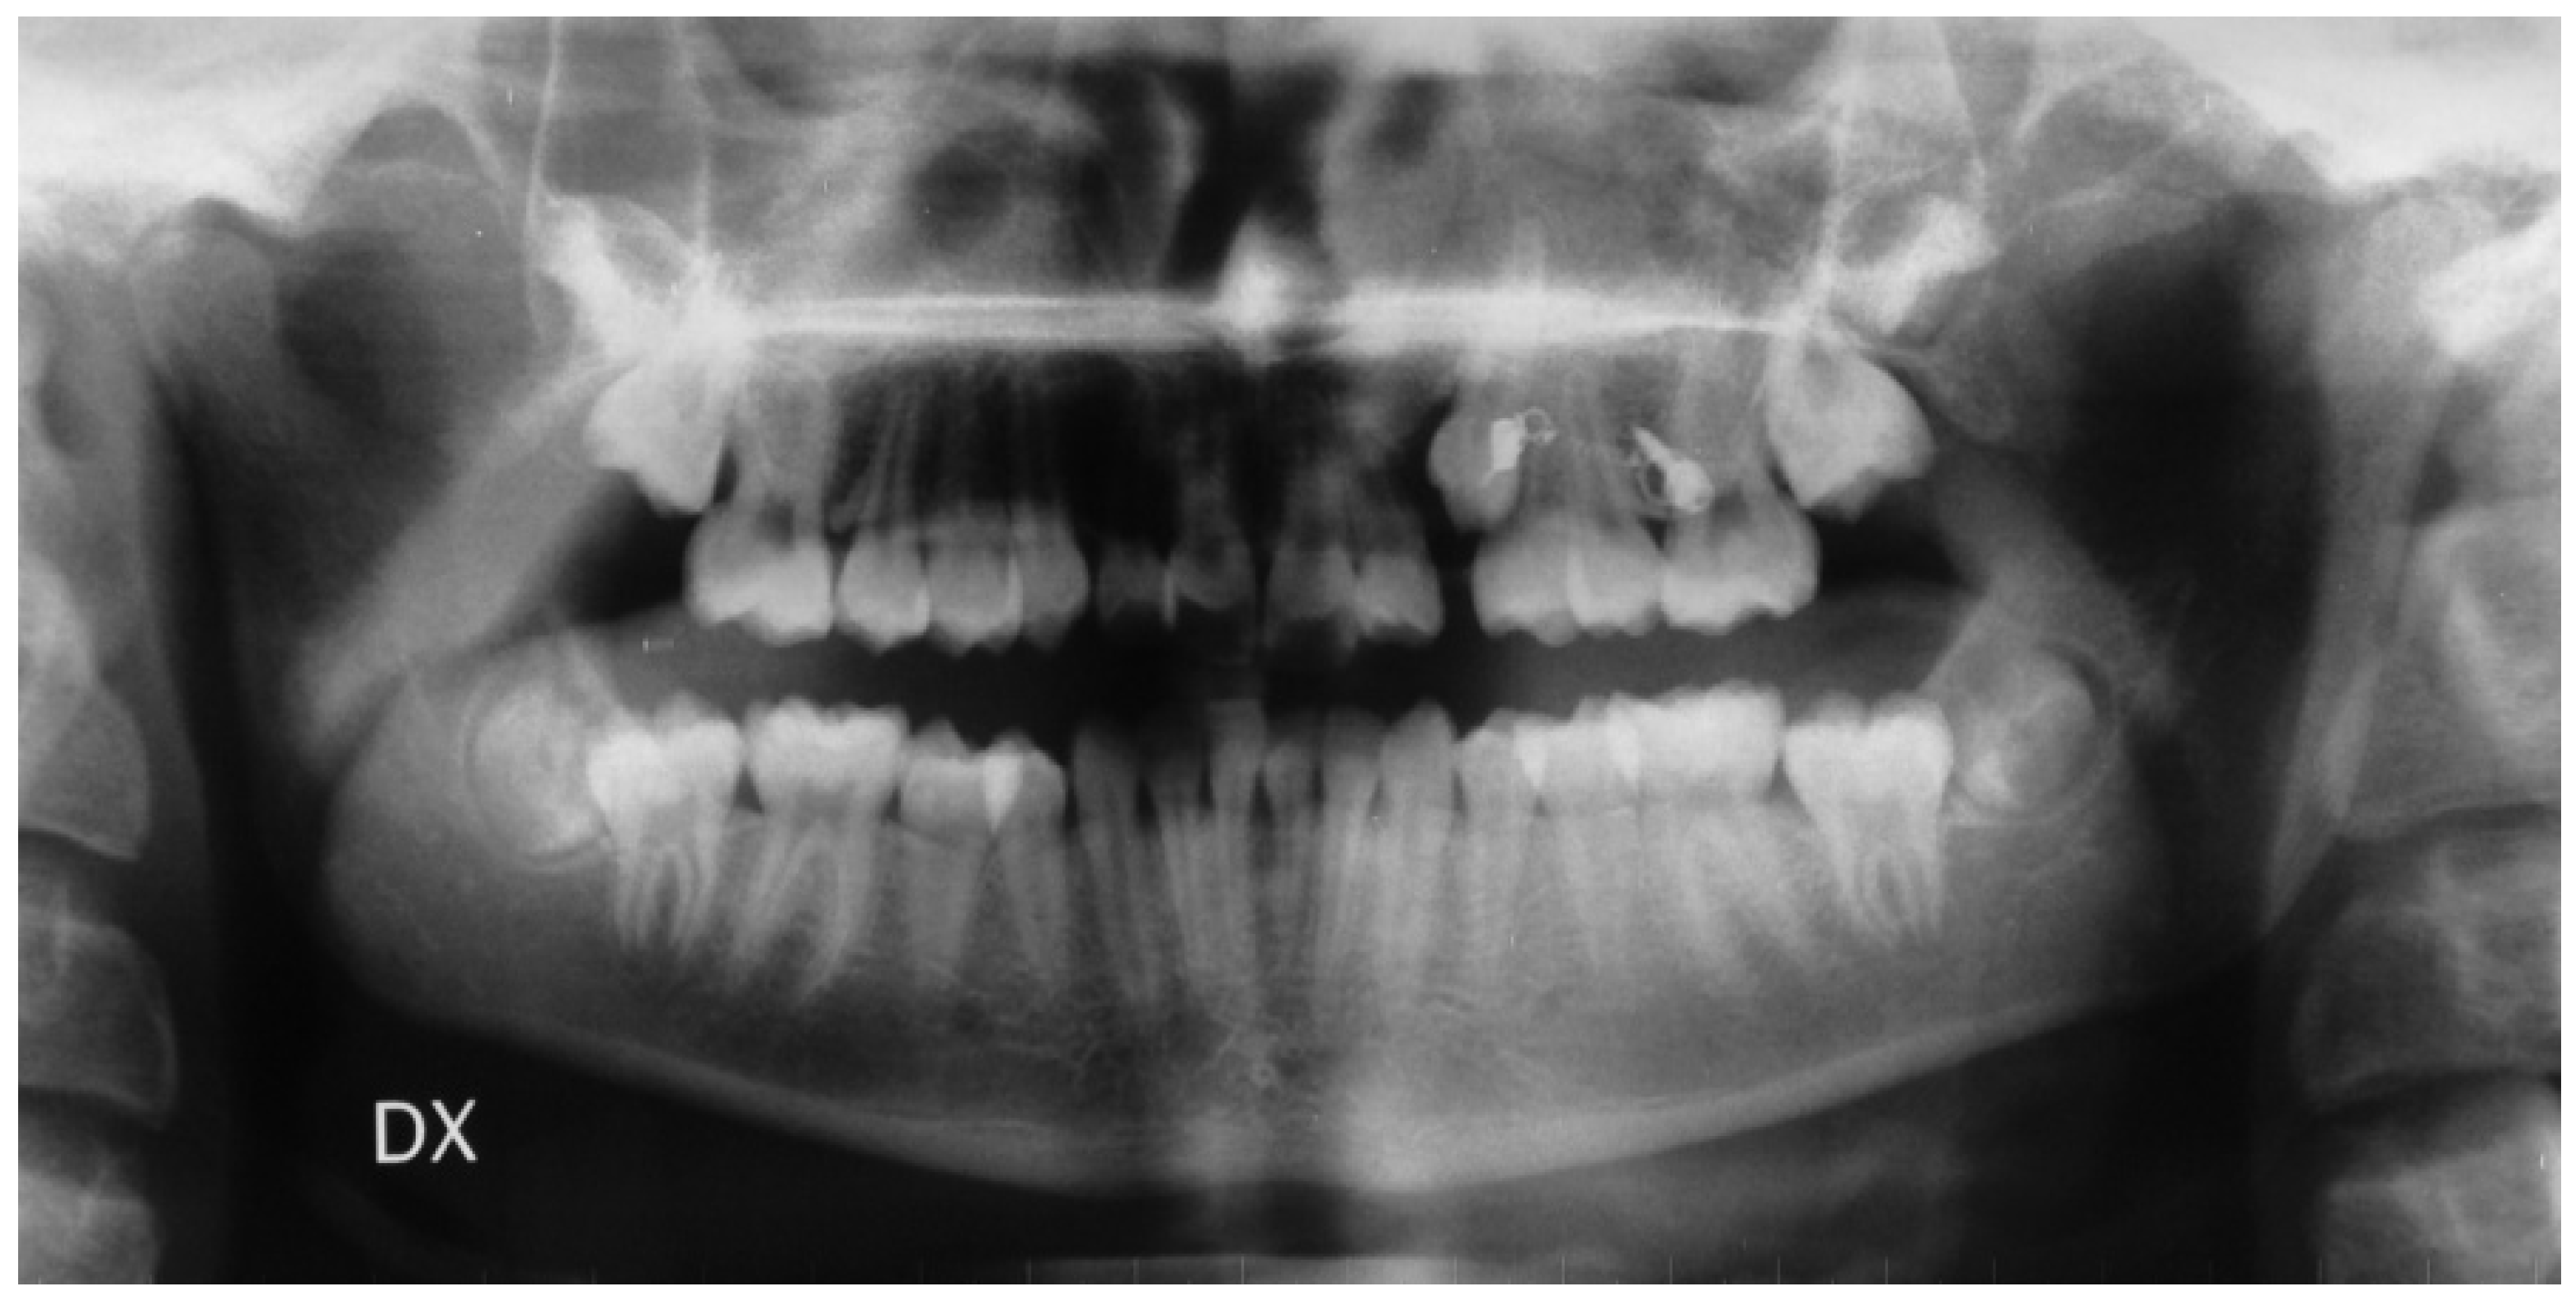

- In the first step, a panoramic radiograph and a teleradiography of the skull in latero-lateral projection is required. The observation of the panoramic radiography should show the position of the impacted canine, evaluating the relationships of the canine crown with the roots of the adjacent teeth, the alpha angle, and the distance of the impacted tooth from the occlusal plane. The cephalometric study of the teleradiography should provide information about the eventually present malocclusion and treatment needed;

- A cone beam CT, eventually limited to the sector of the impacted tooth, is mandatory to evaluate the three-dimensional relationships of the teeth with the adjacent structures and all of the conditions eventually limiting the correct insertion of temporary anchoring devices (TADs) such as anatomical variation of the lateral extension of the maxillary sinus, the availability of correct inter-root space, or the presence of the premolars buds in mixed dentition. The use of a tridimensional imaging is justified from the need of an accurate assessment of the position of the impacted canine and of its relation with the adjacent structures, due to the higher spatial resolution obtained with lower radiation dose [15].

- Adequate/Inadequate Interadicular Space for The Insertion of The Miniscrew: The positioning of TADs requires a careful choice of the insertion site to select a position useful for the traction of the impacted teeth but respectful of the teeth and of other anatomical structures. The right selection of the patient performed through an accurate study of the radiographic images is essential, preferably on a 3D imaging of the interested arch. A correct inter-radicular space between the first molar and the second premolar is necessary and should be selected adding 1 mm of bone width and 0.5 mm of periodontium width on both sides to the screw diameter measurement. If any adequate inter-radicular space is available, as often occurs in the patient with a mixed dentition, the variant of the technique provides an anchorage to the distalizing force by an intraoral device, usually consisting of a palatal bar with rests on the premolars and a vertical vestibular arm to which the closed coil-spring should be fixed by a metal chain. A similar vestibular arm can in the same way be soldered also on palatal expanders devices eventually needed for the orthodontic therapy.